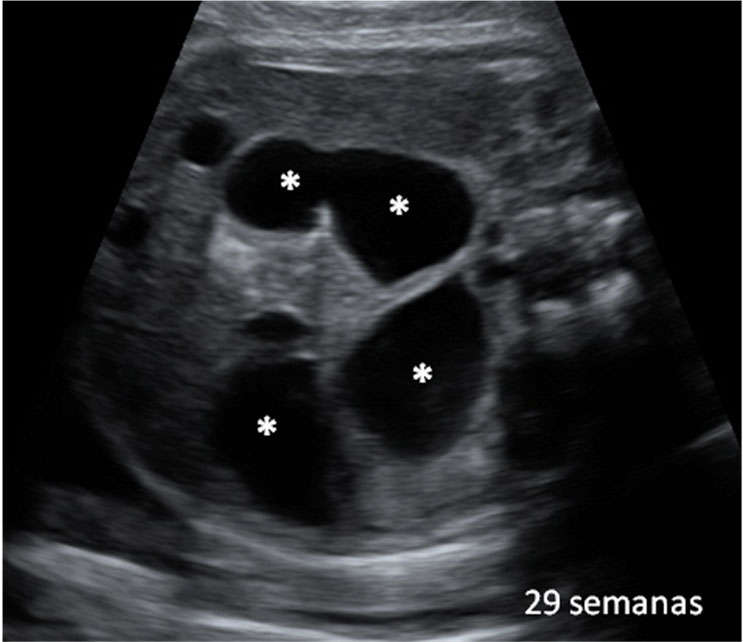

Ecografía Embarazo 4D - SEMANA 20